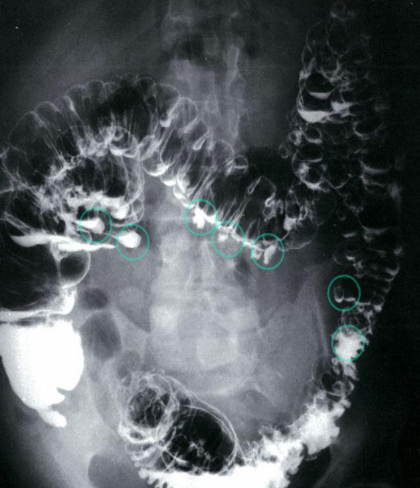

A. Give the name of the imaging examination in the given image. Enema double contrast

B. Give the NAMES of the used contrast media for the examination Barium & air (+ve Vs –ve)

Imaging examination Diverticulosis - Double-contrast barium enema of the colon

Findings or description Multiple diverticula in the colon can be seen (examples circled in green).

Diagnosis Diverticulosis